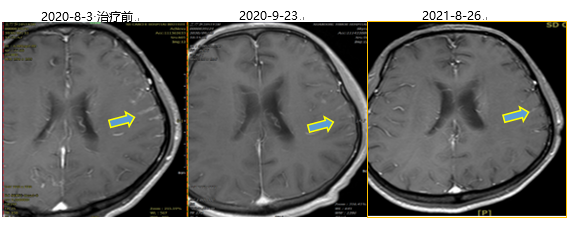

颅脑强化MR:双侧大脑半球及小脑脑膜走行区见线条状及结节状强化,以左颞顶部为著。符合脑膜转移MR表现。

图片YkT帝国网站管理系统

颅脑强化MRI提示:口服阿美替尼2个月后,双侧大脑半球及小脑脑膜走行区见线条状及结节状强化,较前期局部好转;8月26日末次随访时脑室系统大小及形态未见异常。YkT帝国网站管理系统